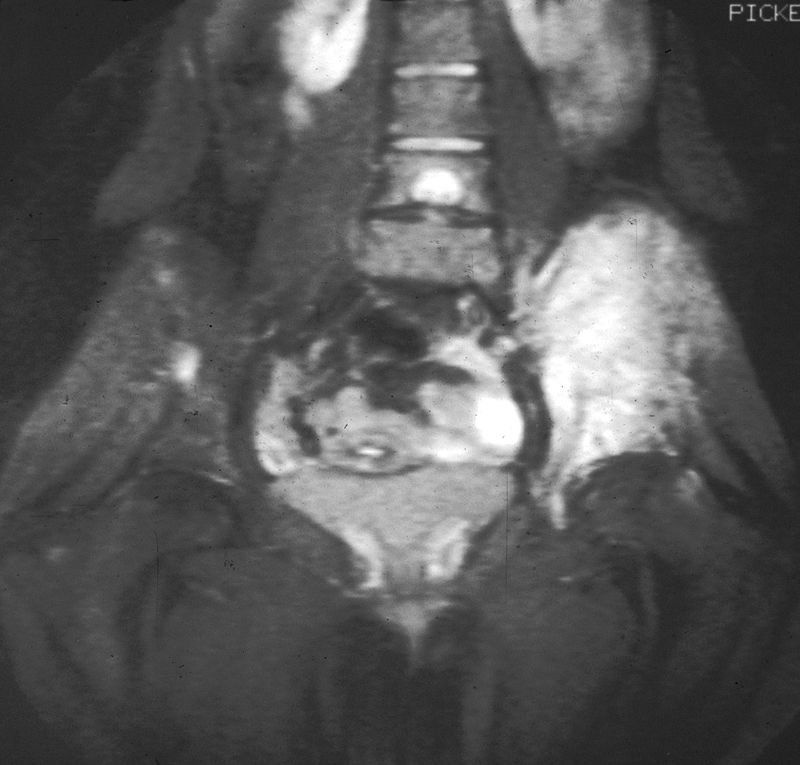

Chondrosarcoma

Chondrosarcoma is a malignant cartilage-forming tumor.

Chondrosarcomas tend to develop in the axial skeleton or pelvic medulla.

Diagnosis of chondrosarcoma is made by biopsy, which shows malignant chondrocytes.